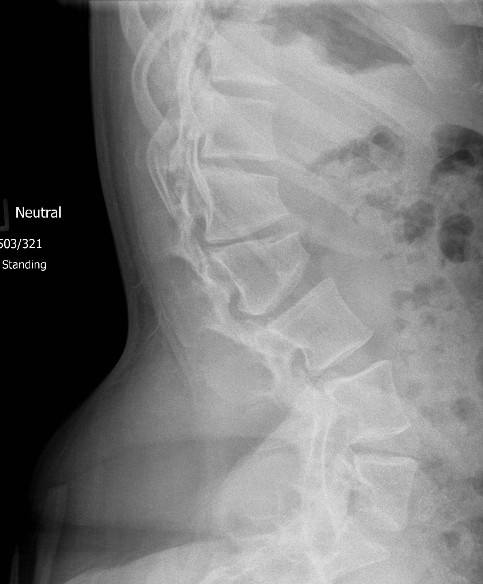

Thoraco-lumbar

Increased lumbar lordosis

Non-rigid TL kyphosis

- usually resolves with ambulation

- due to hypotonia

Spinal canal stenosis

- short pedicles

Platyspondyly

- bullet shape vertebrae

- anterior inferior body beak T12- L2

- posterior scalloping of vertebral bodies